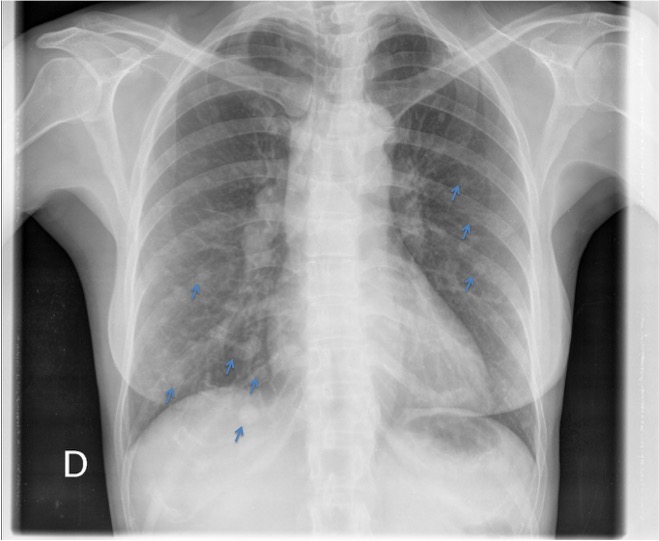

CASO: Febrícula y tos de 4 días de evolución.

Hallazgos:

- En la placa PA se observa una asimetría en los hilios pulmonares, el hilio izquierdo tiene una densidad aumentada.

- Tras examinar la placa lateral se observa un aumento de densidad en la columna que puede ser compatible con una condensación, es el signo de la desnificación vertebral.

SIGNO DE LA DENSIFICACIÓN VERTEBRAL: En la radiografía lateral normal, la densidad de la columna torácica tiende a disminuir desde la parte superior hasta el diafragma; la alteración de ese patrón por la presencia de una densidad superpuesta a la columna, indica la existencia de una consolidación pulmonar. Este signo adquiere especial valor cuando en la proyección posteroanterior la consolidación está oculta en el espacio retrocardíaco o en la base pulmonar.